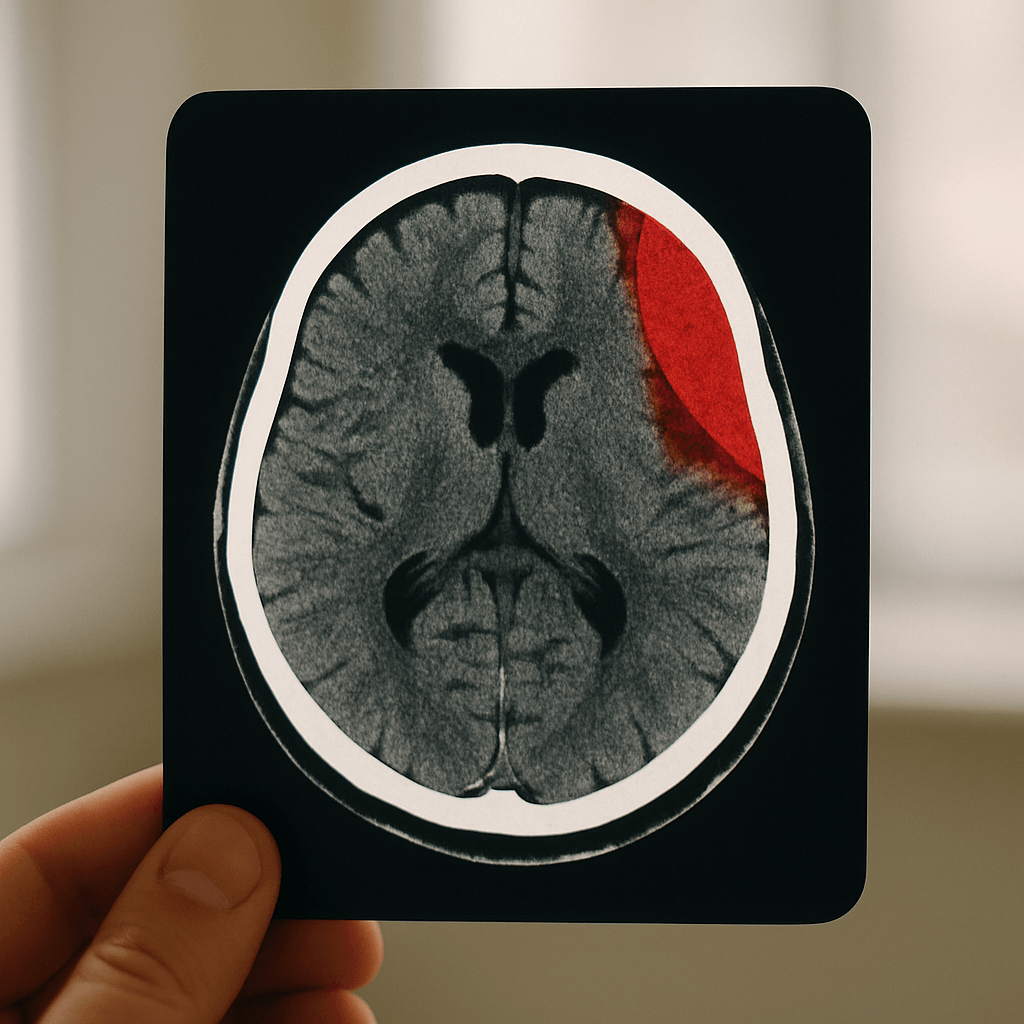

Peut-être pensez-vous : “Un scanner ? Pour un simple bobo ?” Mais le scanner cérébral ou l’IRM sont vos alliés pour lever toute suspicion d’hématome sous-dural chronique. Imaginez-les comme des détectives high-tech. ⚔️

Scanner ou IRM : lequel choisir ?

En cas de besoin rapide, le scanner est souvent la première étape 🏆. L’IRM, quant à elle, offre une profondeur d’image, parfaite pour les cas complexes.